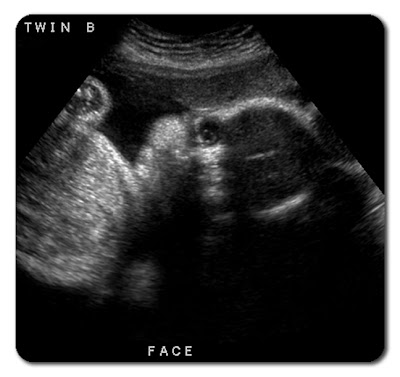

This is our little boy. He weighs about 3 pounds and 9 ounces. He measures two weeks earlier than our girl. He is also laying sideways with his head on my left.

The ultrasound technician said his eyes are open in this picture.